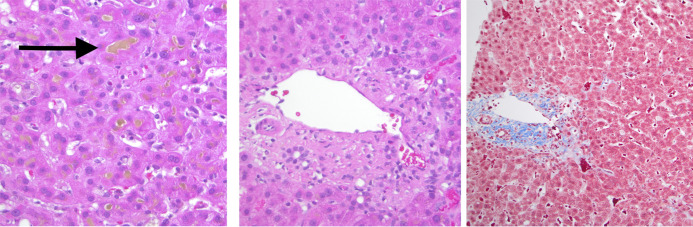

选择性雄激素受体调节剂(SARMs)是调节雄激素活性的合成代谢化合物。尽管没有得到食品和药物管理局的批准,但它们已经越来越多地用于补充剂中,以提高性能和肌肉生长。它们的使用与肝损伤的胆汁淤积模式有关,类似于合成代谢雄激素的使用。治疗主要是支持药物停止和胆汁淤积可能需要几周到几个月的正常。我们提出了一个非典型的延长胆汁淤积的情况下,容易获得的选择性雄激素受体调节剂被称为RAD-140,成功地管理与皮质类固醇引起的。

Selective androgen receptor modulators (SARMs) are anabolic compounds that modulate androgen activity. They have been increasingly used in supplements to enhance performance and muscle growth despite not being Food and Drug Administration approved. Their use has been associated with a cholestatic pattern of liver injury similar to that seen by anabolic androgens. Treatment is primarily supportive with drug cessation and cholestasis can take weeks to months to normalize. We present an atypical case of prolonged cholestasis caused by the readily available selective androgen receptor modulator called RAD-140 that was successfully managed with corticosteroids.